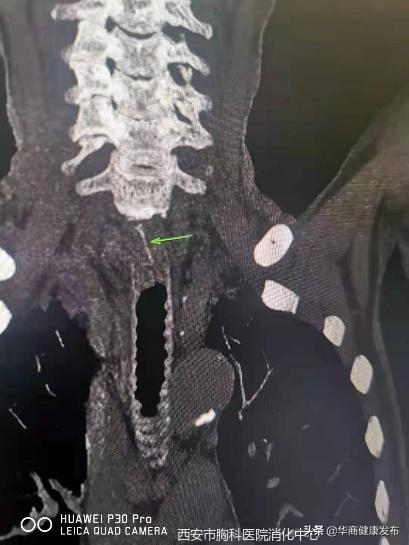

7月13日下午,西安市胸科医院消化内科门诊来了一位82岁的老人,因为进食过程不小心,一根鱼刺卡在了食管内已经超过24小时,就诊多家医院,无法取出异物。张蓉医生仔细询问了患者病情,迅速为老人完善了内镜和异物取出术的相关检查,以尽快解除险情,避免异物进一步扎穿食管,增加治疗的创伤和复杂性。

情况紧急,张蓉医生立即为老人行胃镜下异物取出术,仅用10分钟,张蓉医生用异物钳将鱼刺成功取出。老人安全返回病房,经观察没有任何不适,恢复正常进食。

鱼刺约1.5cm长,位于颈7水平,食道前壁偏右侧